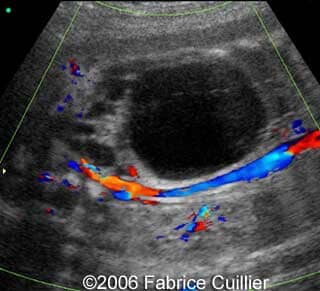

• an abnormal polycystic left kidney (34 X 17 mm) with an abnormal corticomedullar differentiation. This kidney was on the lumbar fossa.

At 24 and 26 weeks, the left kidney lesion had increased. At 34 and 37 weeks, the anomalies were the same. The baby was delivered vaginally (male, 3000 g). At day five, the kidney abnormalities were confirmed. Nevertheless the creatinine level was normal. One month later, a scan revealed a normal right kidney (50 mm) and a left kidney with cysts. The creatinine level was in the normal range. The child was operated (left nephrectomy). The diagnosis of multicystic kidney disease was confirmed.